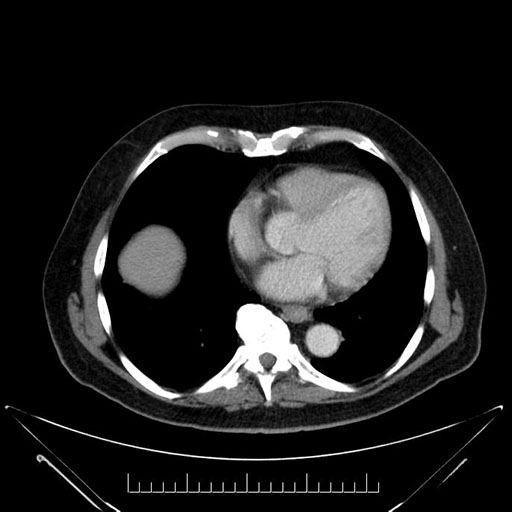

Imaging Analysis

Look through the patient's CT scan to identify any areas of concern for the necessary procedure.

Based on your CT findings, which issue(s) would give reason for "planned slowing down moment(s)" in this case?